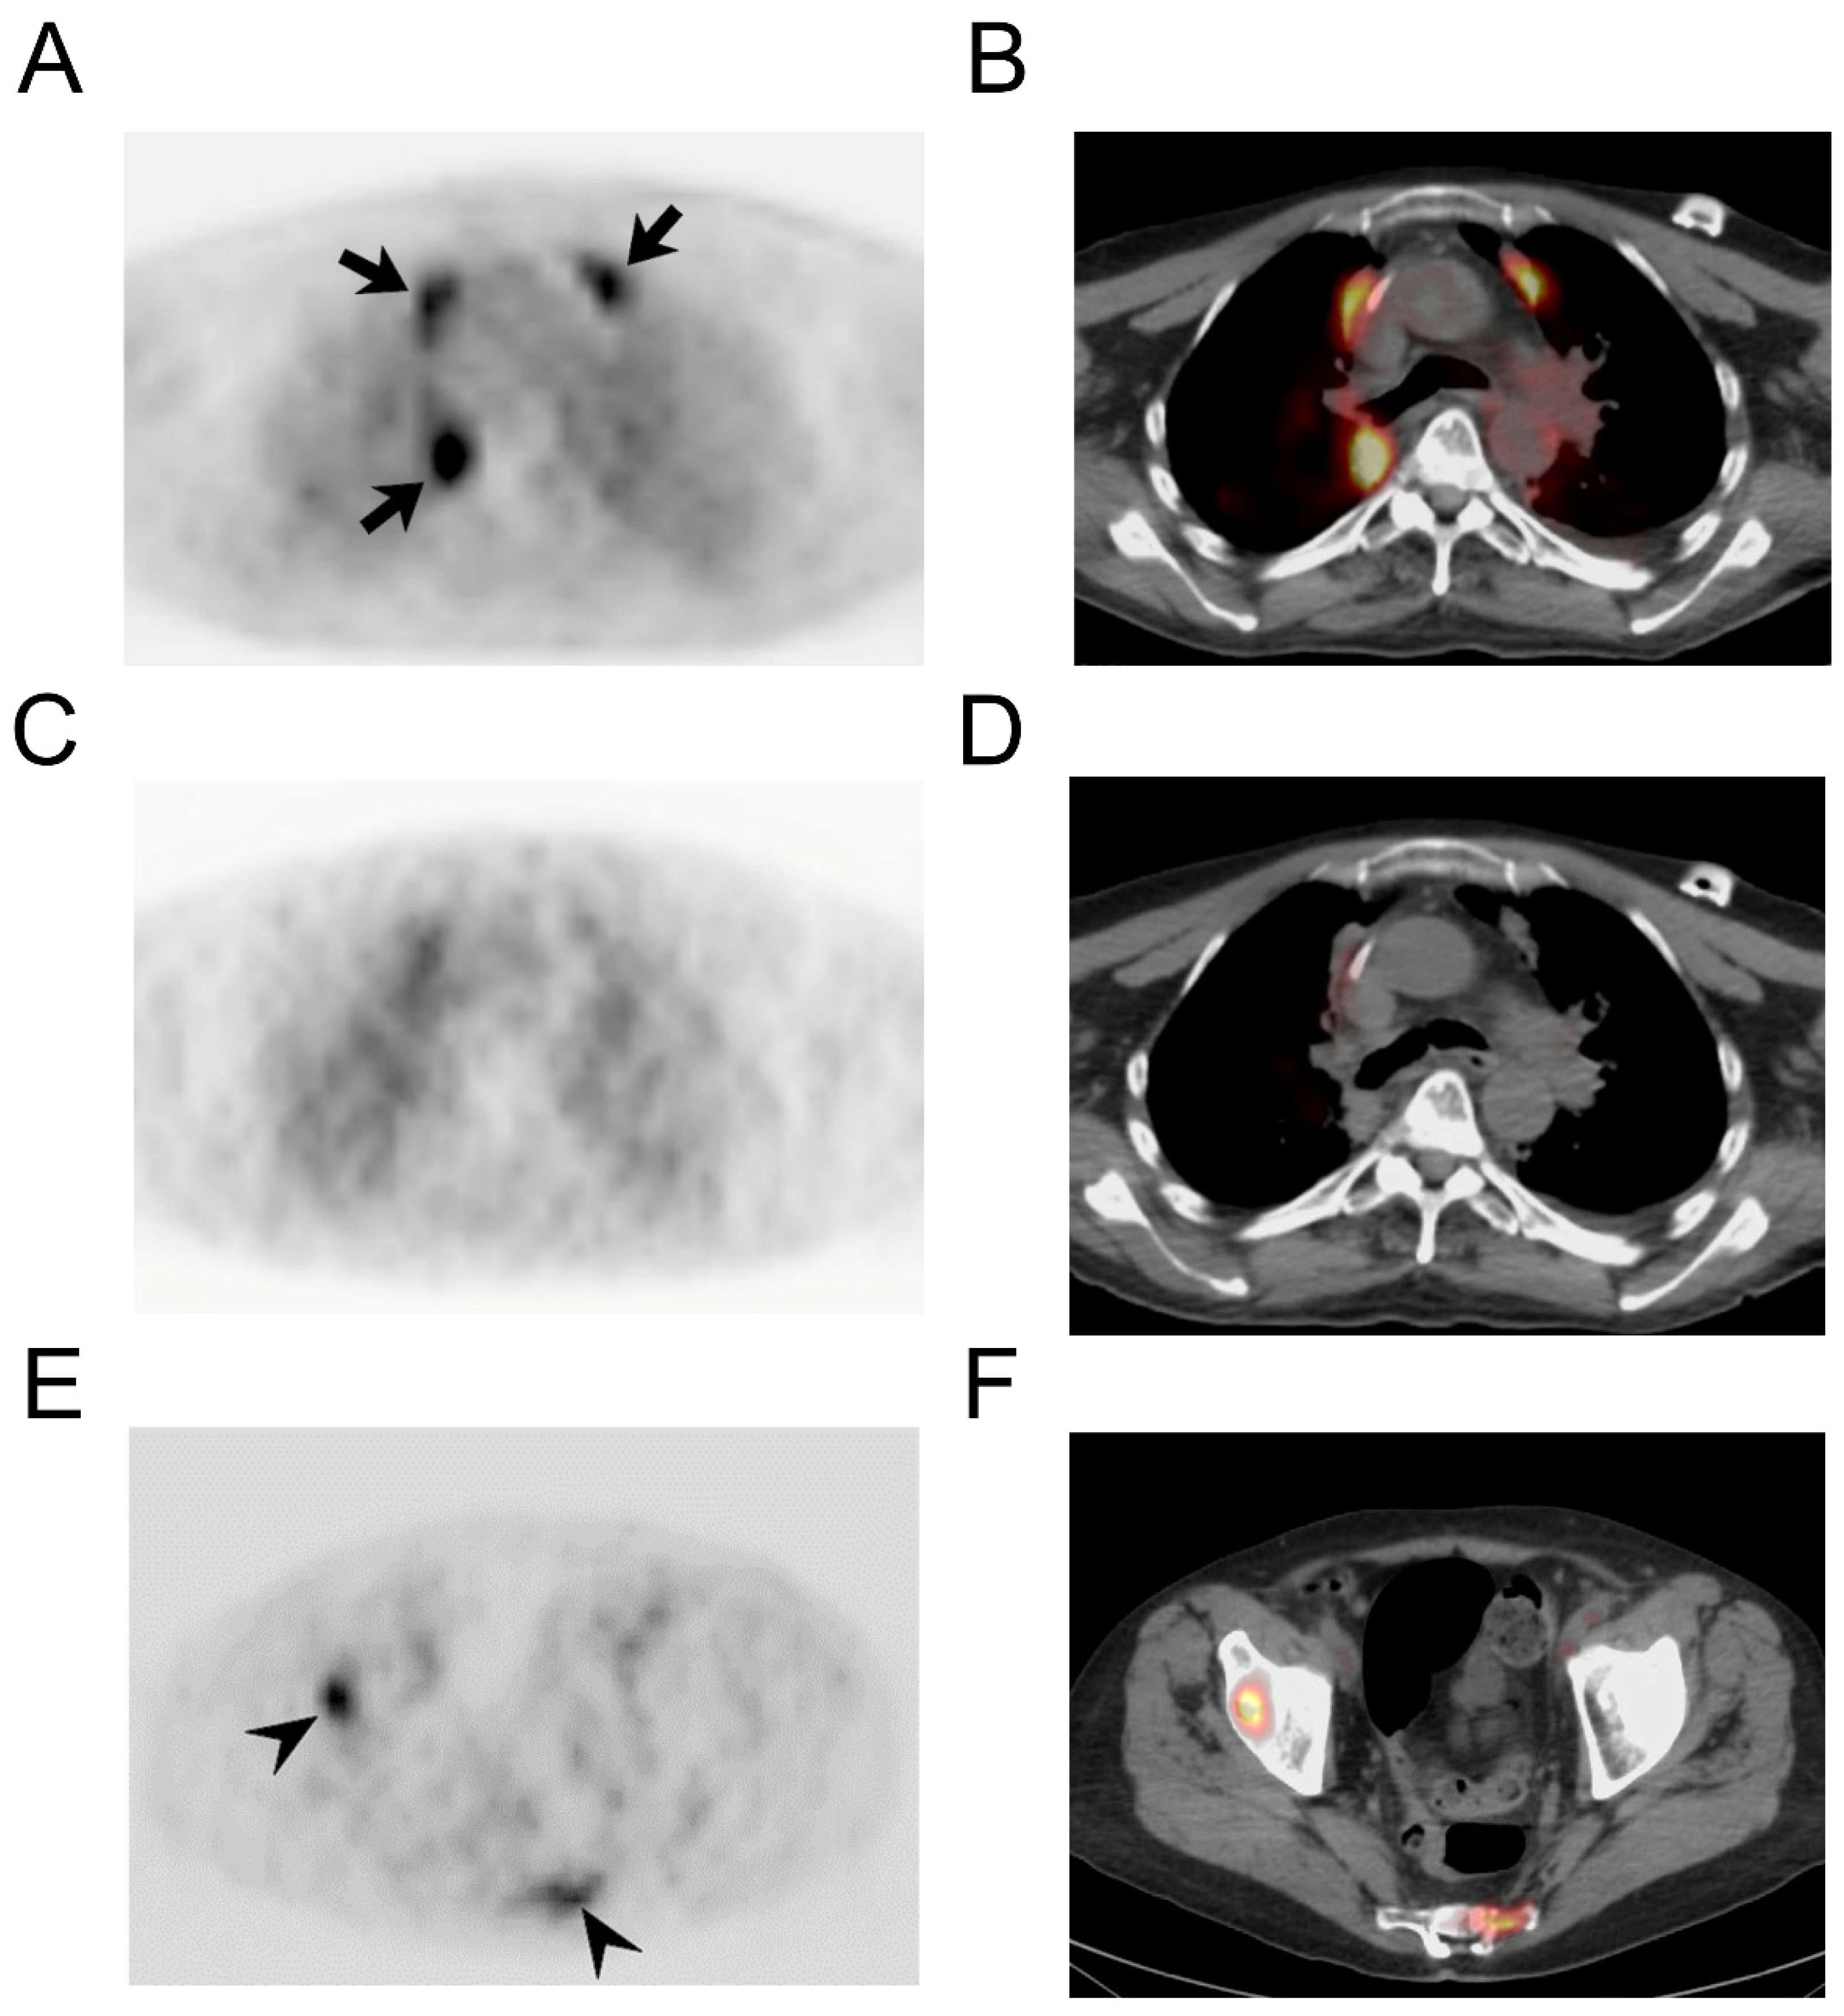

At this preliminary stage of investigation, the size threshold for CLR1404 detection of metastatic pulmonary nodules remains uncertain. In one patient with micronodular (miliary) pulmonary metastases, neither [18F]FDG nor [124I]I-NM404 PET imaging showed detectable abnormal activity. Post-treatment changes in the lung from radiation or chemotherapy are a recognized cause of false-positive uptake on [18F]FDG PET (Figure 4) However, NM404 showed avid uptake within sites of active osseous metastatic disease. The activity within lytic bone metastases from a variety of primary cancers corresponded with hypermetabolic FDG foci. In one case, a lytic vertebral lesion representing a solitary focus of osseous metastatic disease was identified by [124I]I-NM404 PET but missed on the clinical CT interpretation (Figure 4). In some cases, with longstanding blastic or sclerotic osseous lesions, [124I]I-NM404 uptake was not appreciated, which appeared to be discordant with FDG PET and [99mTc]Tc-MDP skeletal scintigraphy in some cases. It is unclear whether this discordance corresponds to [124I]I-NM404 false-negative detection or false-positive reactive activity from the clinical exams related to treatment response or “flare” phenomenon from bone remodeling.

Figure 4. Radiation change and osseous metastatic disease in a 65-year-old man with bronchogenic carcinoma. PET (A) and fused PET/CT (B) images using [18F]FDG PET shows abnormal linear paramediastinal activity (arrows), characteristic of radiation therapy. Corresponding PET (C) and fused PET/CT (D) images using [124I]I-NM404 do not show florid uptake in this reactive process. However, [124I]I-NM404 PET did demonstrate multifocal osseous metastatic disease (E,F), arrows.